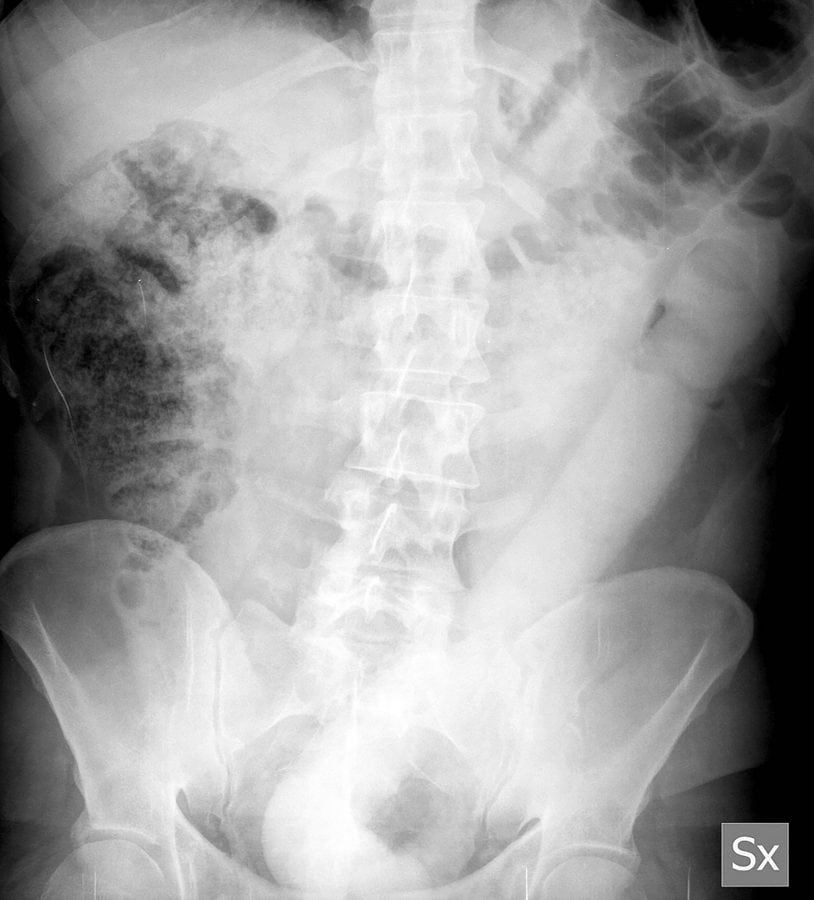

After complaining of mild abdominal pain an X-ray revealed the 23 inch (60cm) object in his colon and he was sent to the endoscopy unit where surgeons attempted to remove it.